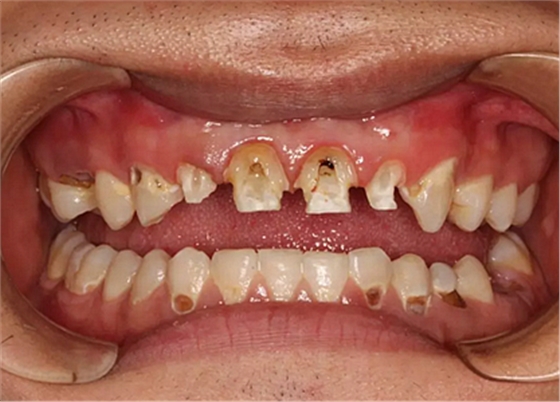

現(xiàn)在剩下的任務就是為我其他的兄弟姐妹們治療了。需要做根管的做根管,需要做冠的做冠,需要樹脂充填的做樹脂充填。前前后后主人帶我們進行了12次的復診,歷時6個月,現(xiàn)在的我們是這樣的

再來看看曾經(jīng)的我們

經(jīng)歷了如此長久的治療,主人應該也是吸取了教訓,或許以后會改了不良的生活習慣,而我們經(jīng)歷了這段涅槃之旅,雖然也煥然一新,重塑了容顏,卻也是歷經(jīng)辛苦,如果主人能好好待我們,其實這樣的痛苦本不需要經(jīng)歷。